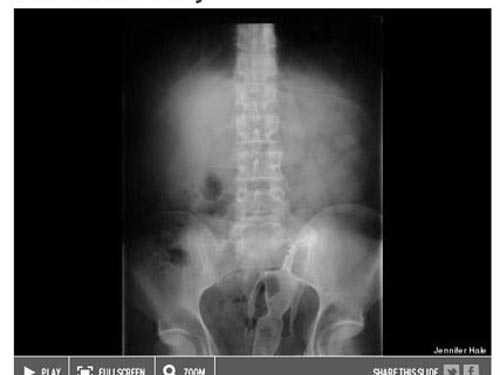

![]() |

| Các bác sĩ không hiểu làm sao búp bê Barbie có thể lọt vào cơ thể người |